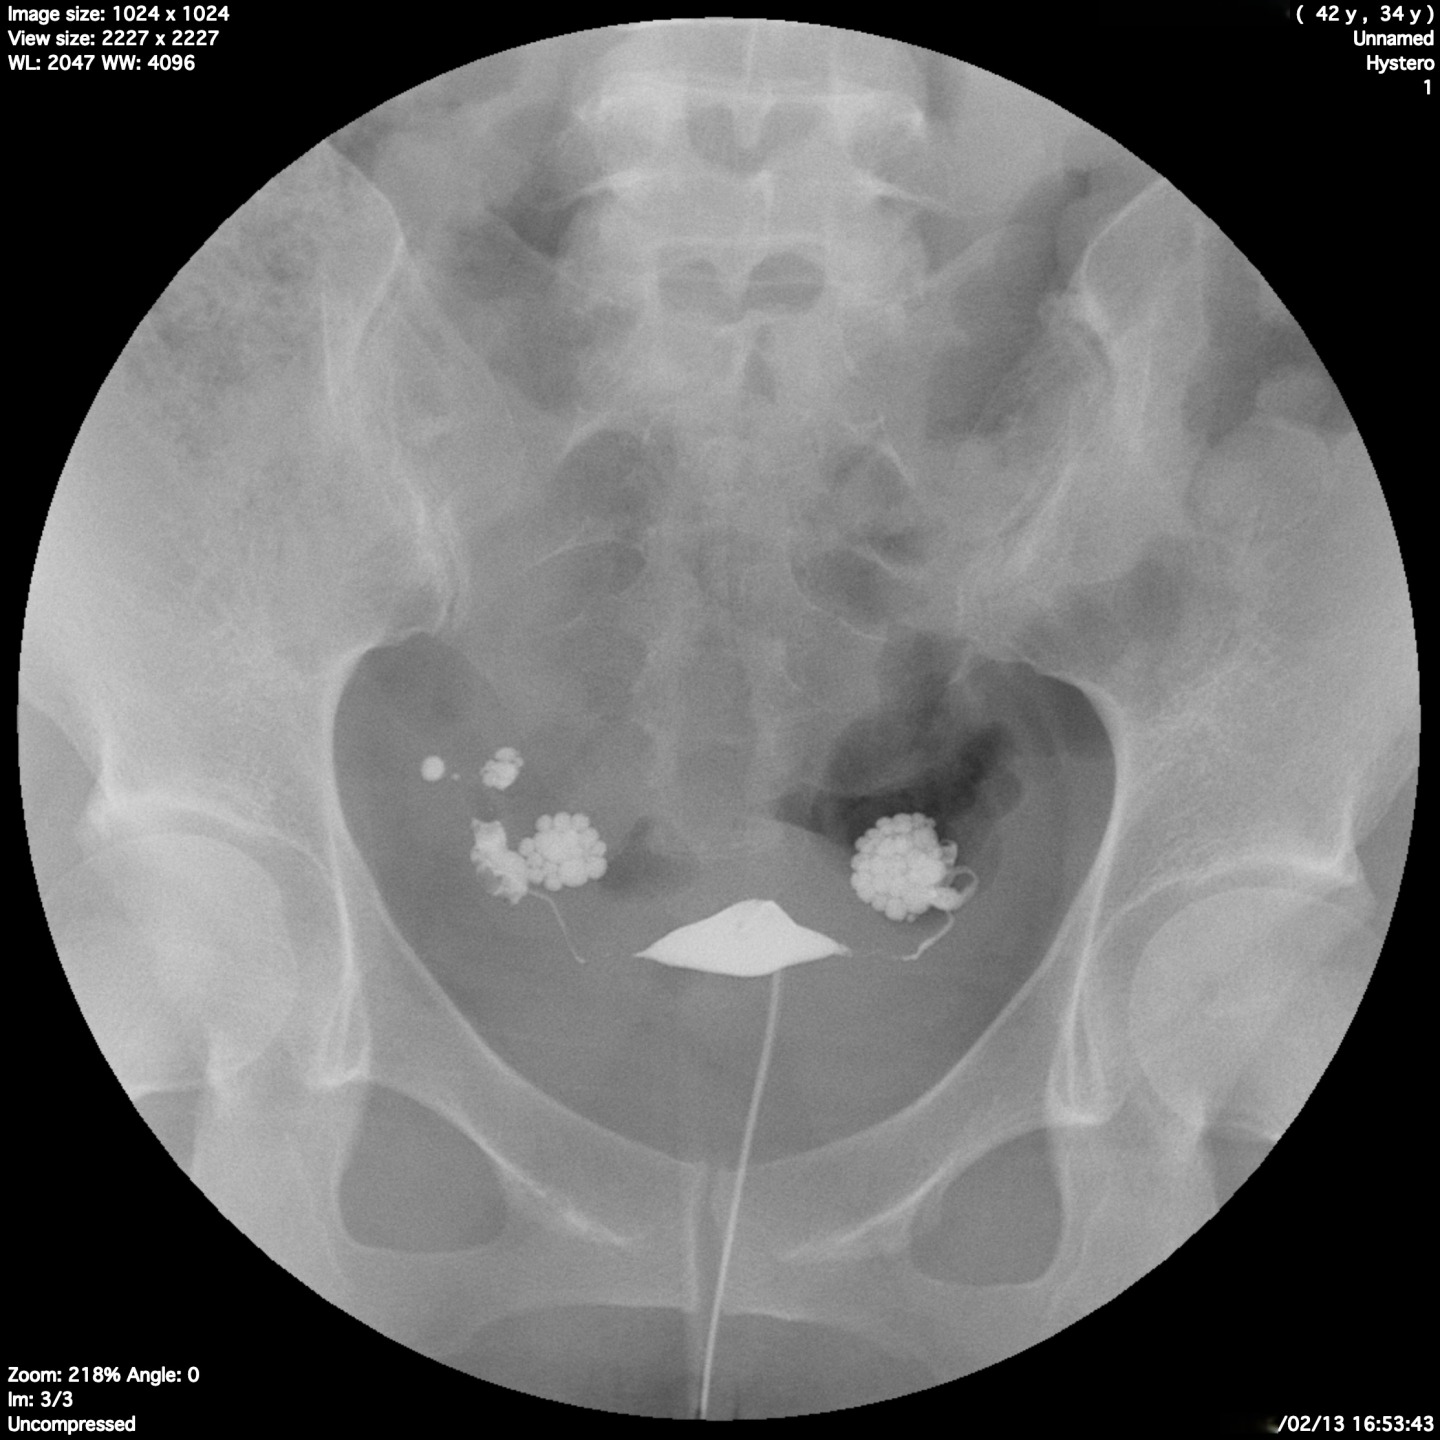

下の症例は34歳の妊娠経験なし

クラミジア抗原検査陰性、

通水検査検査にて抵抗なし、通過性ありと診断され

タイミング療法 5周期 人工授精 4周期 しても妊娠に至らず体外受精目的にて当院紹介受診された患者様です。

当院でのクラミジア抗体検査ではIgG(+) IgA(+)を確認し、クラミジア治療を行い油性造影剤にて卵管造影を行った結果です。

一見卵管通過性があるように見えますが卵管采(卵管の末端)に貯留所見を認め、腹腔内に流出していません。

翌日の残像撮影では

両側の卵管采における貯留所見は移動せずそのまま残留している所見を認め、卵管留水症の診断になりました。この場合おそらくは通水検査や超音波造影剤による検査では診断ができなかったと思われます。

これではタイミング療法や人工授精では妊娠はほぼ不可能であり、体外受精もしくは手術的な対応が必要となります。